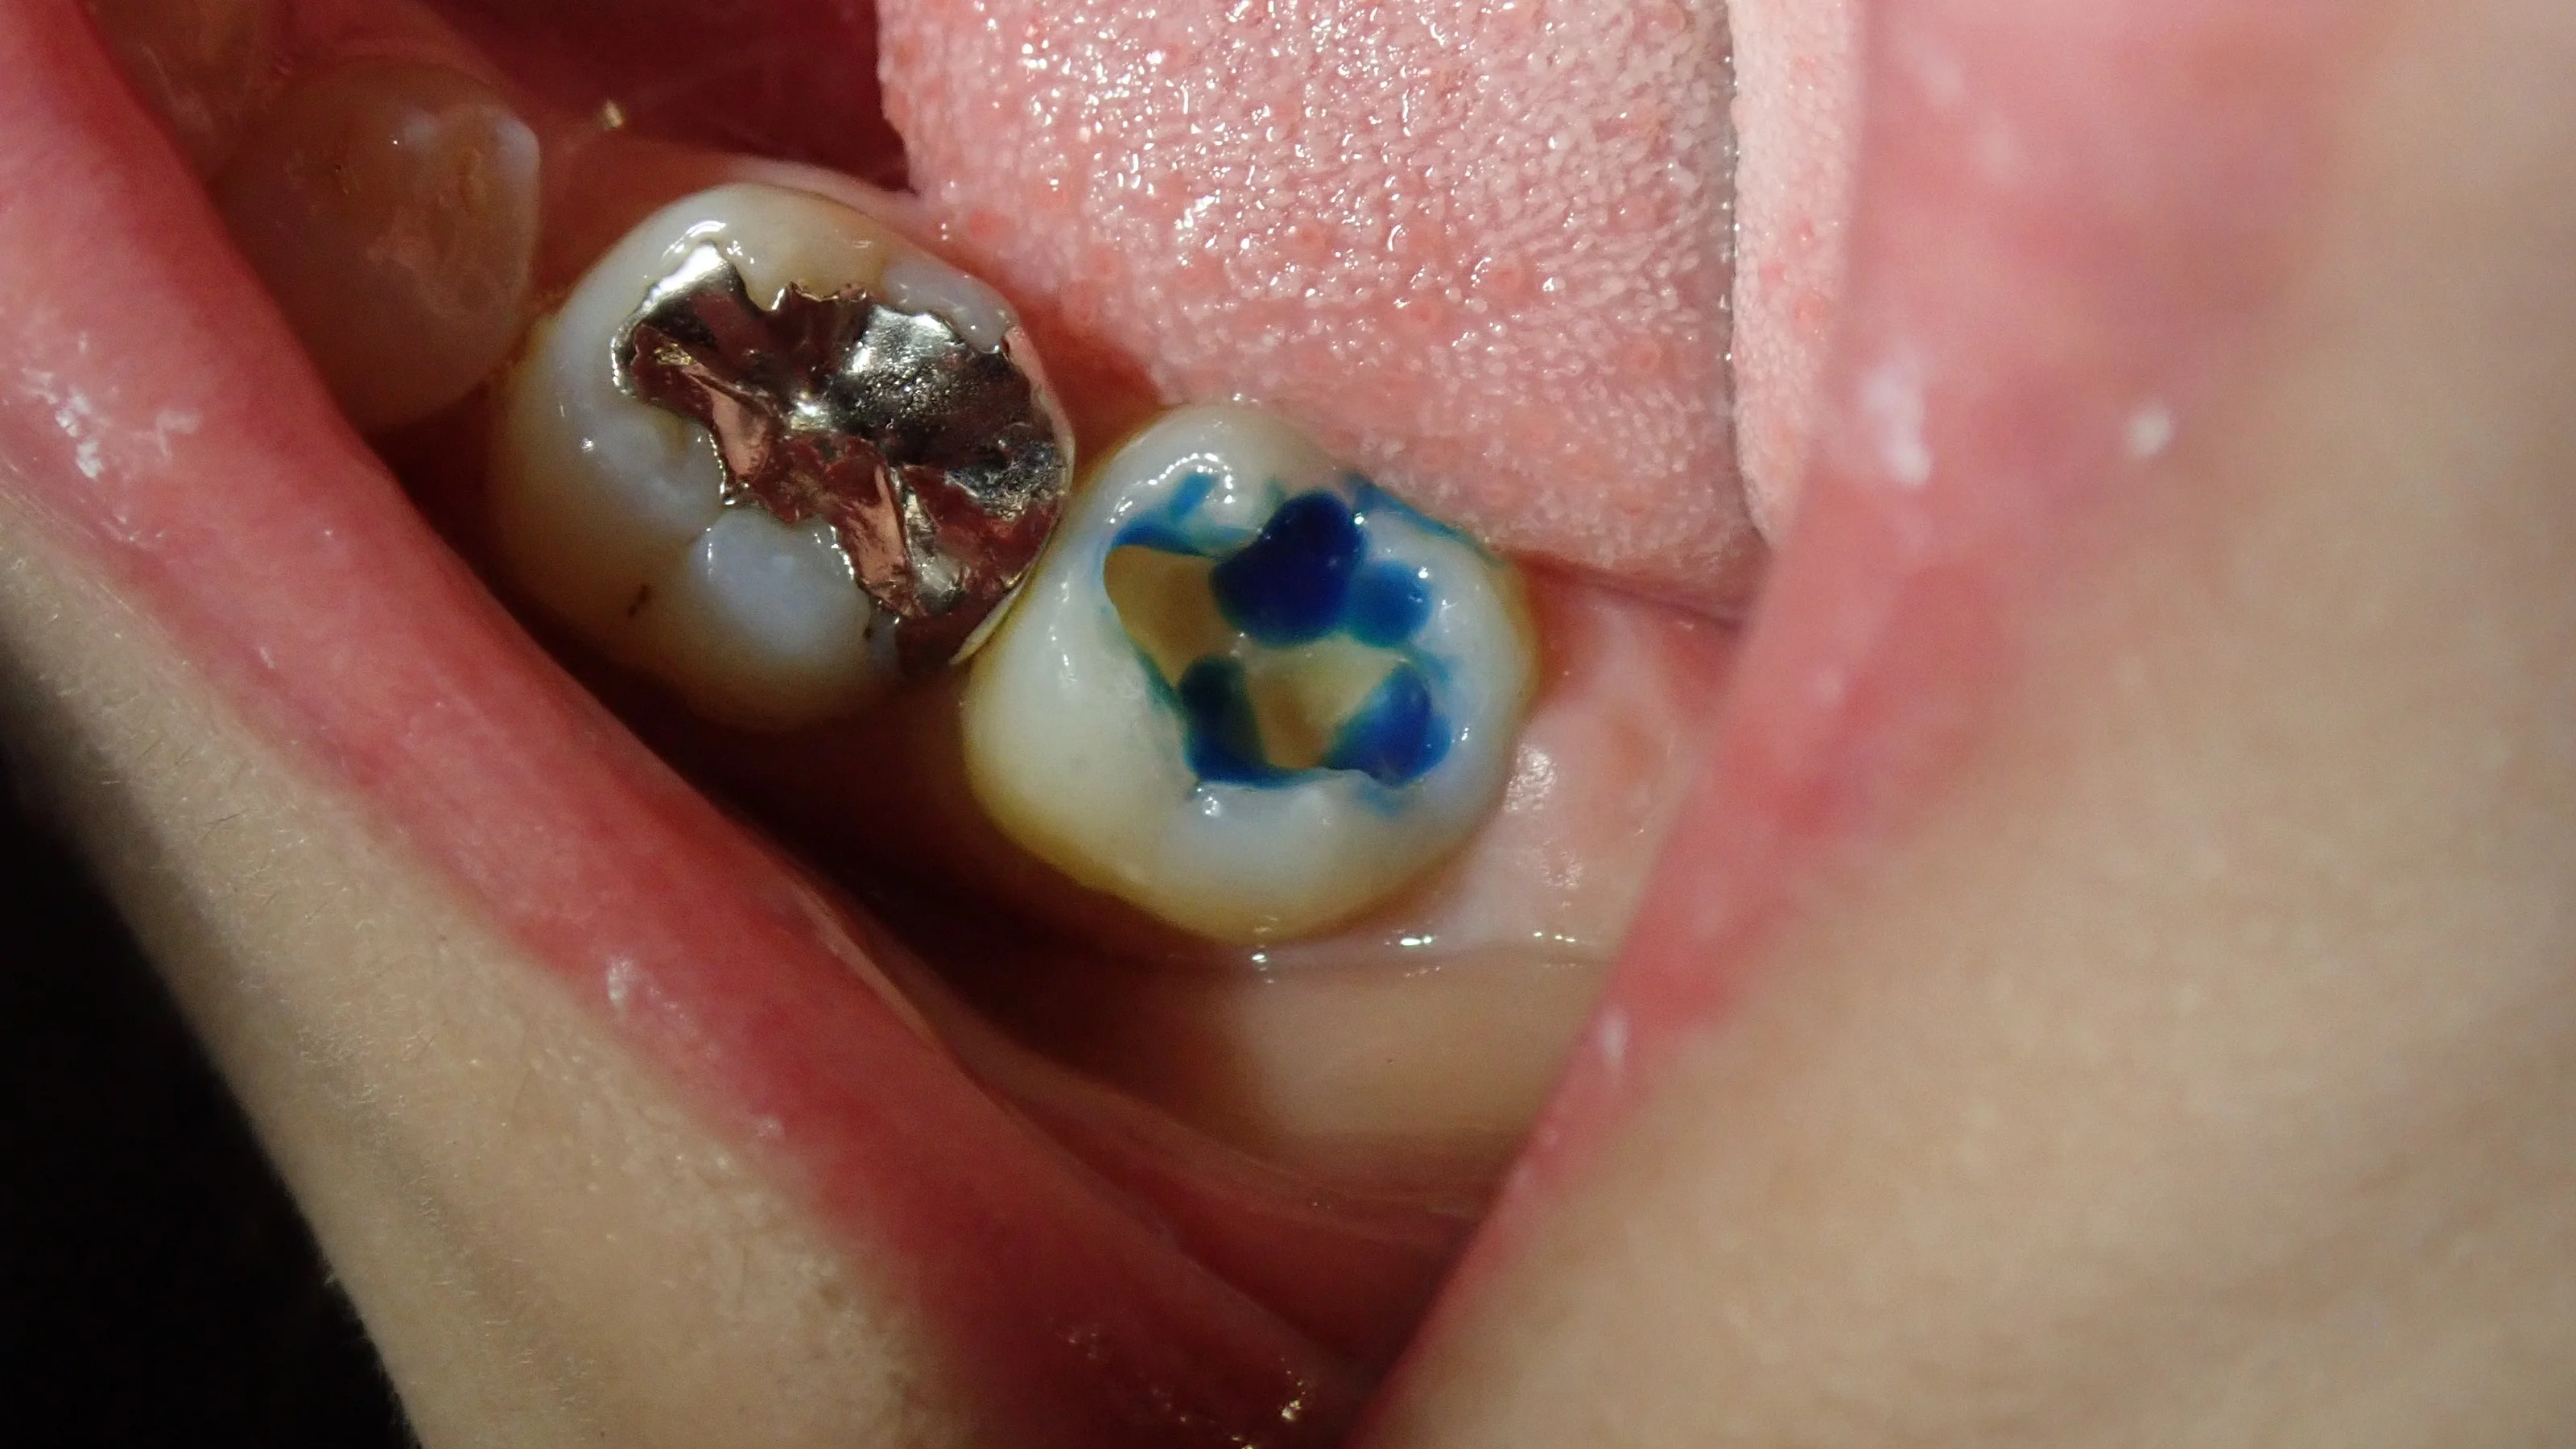

歯の表面処理をしている時に気付いてそこから取りました。

なので、

詰める前。

詰めた後。

って感じになっちゃいました・・・。